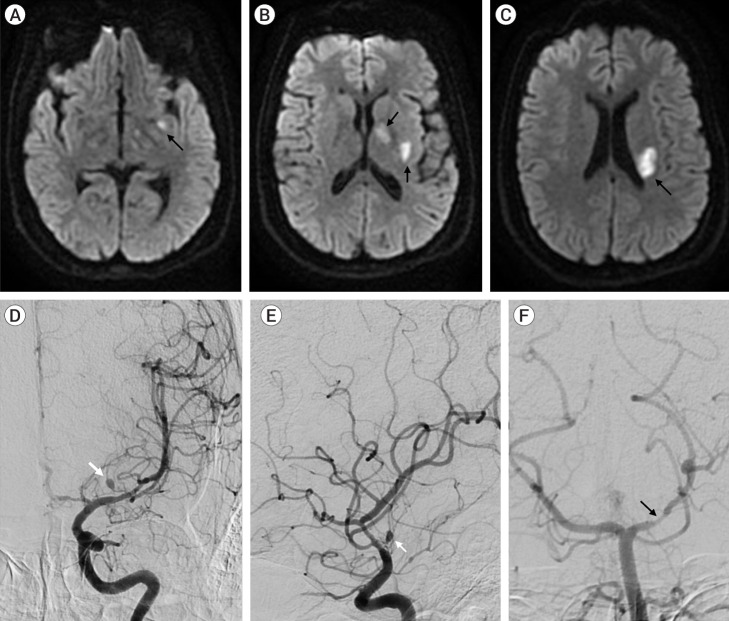

Primary Angiitis of the Central Nervous System (PACNS) is an uncommon disease with kaleidoscopic clinical manifestations. Ischemic strokes are commoner than their hemorrhagic counterpart. Intracranial pseudoaneurysms are rarely reported in PACNS cohorts. We hereby describe the case of a 39-year-old female, who presented for evaluation of acute onset of left middle cerebral artery (MCA) ischemic stroke, with cerebral angiogram showing multifocal stenosis and irregularities in intracranial blood vessels with an aneurysm arising from the lenticulostriate branch of the left MCA M1 segment. A diagnosis of probable PACNS was made and patient initiated on immunomodulatory treatment with corticosteroids. 12 weeks follow up neuroimaging studies revealed resolution of the previously described intracranial aneurysm, thereby postulating the possibility of a pseudoaneurysm related to the underlying angiitis.